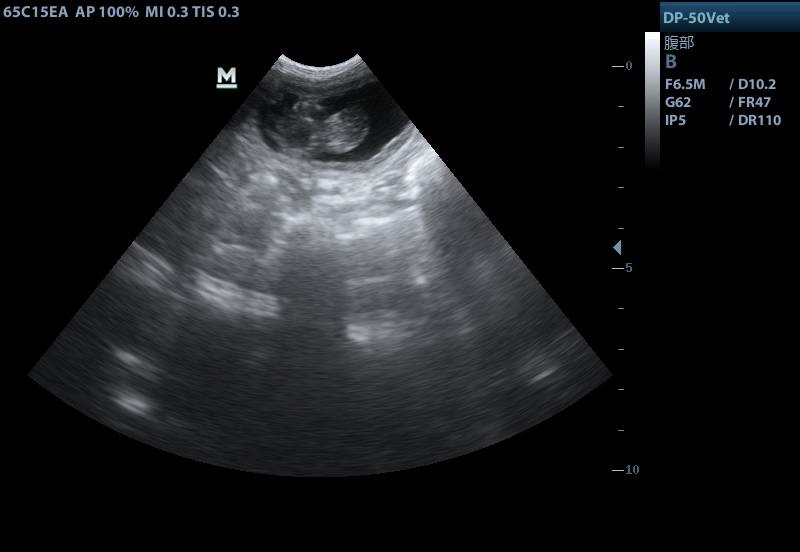

妊娠中の代理出産メス貓の超音波畫像。畫像提供は青島農業(yè)大學